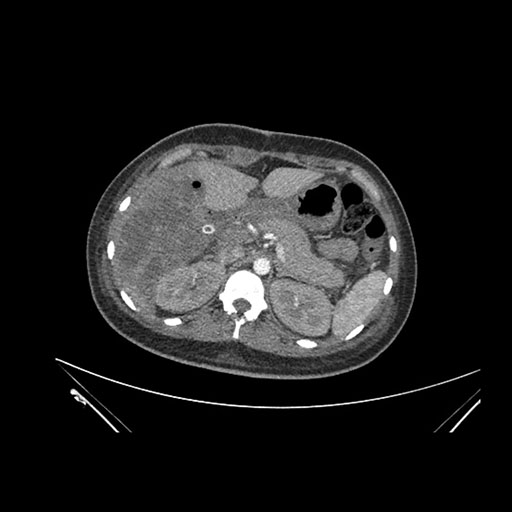

Axial Venous

Imaging analysis

Based on initial findings, which issue(s) would you be most concerned about?